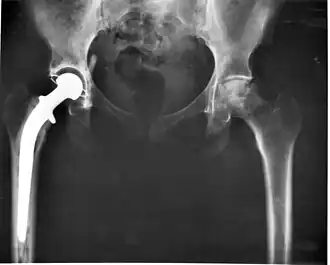

Cette découverte l'amène à commencer à chercher une substance glissante qui pourrait être utilisée pour l'emboîture d'une opération de remplacement total de la hanche. Le Polytétrafluoroéthylène (PTFE, également connu sous le nom de Téflon) semble répondre à cette exigence. Après quelques expériences apparemment réussies avec le matériau, il l'adopte pour ses chirurgies de remplacement de la hanche. Elles sont réalisées comme suit : écarter la tête du fémur ; le remplacer par un implant métallique qui est fixé avec du ciment acrylique ; et, à l'aide d'une douille acétabulaire en PTFE, insertion de l'implant dans l'acétabulum[25].

Au début, le résultat semble satisfaisant, cependant, environ un an après les premières opérations (vers 1960), il s'avère que le PTFE n'est pas un matériau adapté. Il présente des signes d'usure et, surtout, sa réaction avec les tissus mous provoque la formation de masses granulomateuses qui nécessitent dans presque tous les cas une nouvelle intervention pour permettre leur élimination. Ce revers dans les recherches de Charnley l'affecte pendant un certain temps[26].

Sa détermination le pousse à chercher un matériau alternatif. Il continue à tester divers matériaux, jusqu'à ce qu'un vendeur l'approche en lui proposant du polyéthylène à poids moléculaire ultra élevé (UHMWPE), qu'il rejette en raison de son manque de compréhension du problème; son assistant lui dit en privé qu'il s'efforcerait de le tester[27]. C'est un heureux hasard, et il saisit immédiatement le potentiel du HMWP ; après quelques tests, Charnley l'implante pour la première fois en novembre 1962[28]. Conscient de son échec précédent avec l'emboîture en PTFE, il attend un an, période pendant laquelle il observe soigneusement l'état de ses patients. Cinq ans plus tard, lorsqu'il est convaincu que le HMWP est un matériau sûr, il annonce sa découverte, permettant à d'autres chirurgiens de l'utiliser[29]. Au fil du temps, le nombre d'opérations augmente et Charnley conçoit une machine qui fabrique mécaniquement des prothèses et des emboîtures, ainsi qu'un appareil pour évaluer les patients pour leurs troubles de la hanche avant et après l'opération[30].

Il collabore très étroitement avec la firme Chas. F. Thackray Ltd à Leeds, à qui il a demandé pour la première fois de fabriquer des instruments pour lui en 1947. Charnley affine son opération de remplacement de la hanche tout au long de sa longue association avec Thackray's et travaille toujours sur des améliorations à sa mort. Au début, Thackray fabrique les tiges en acier inoxydable, tandis que Charnley fabrique lui-même les douilles, en les tournant sur un tour dans son atelier à la maison. Plus tard, ses techniciens fabriquent des instruments sous étroite surveillance, puis Thackray les fabrique. Au fil du temps, Thackray apporte ses propres suggestions de conception; cet échange continu d'idées est un facteur important dans l'avancement de l'opération de la hanche[31].

Charnley est convaincu que la meilleure façon de fixer la prothèse dans le fémur est d'utiliser du ciment osseux qui agit comme un coulis plutôt que comme une colle et qui emboîte les deux parties[32].